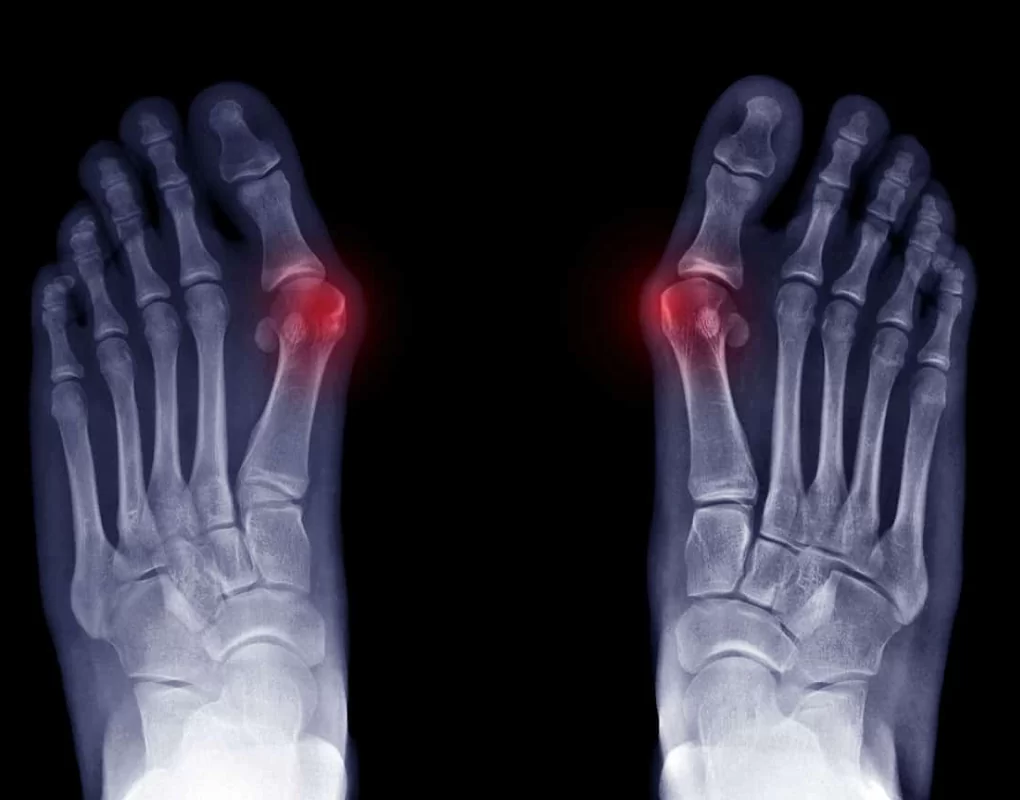

Regular checks and x-rays are recommended to prevent joint damage. Treatment options include changes in foot wear, orthotics, regular exercise, padding and active modifications such as standing or walking for long periods of time.

A bunion is a bony bump that forms at the base of the big toe where it meets the foot. The big toe may start to angle toward the second toe, and you may notice a visible lump, redness, swelling or rubbing in shoes. If you are unsure, a podiatry assessment can confirm whether you have a bunion and how advanced it is.